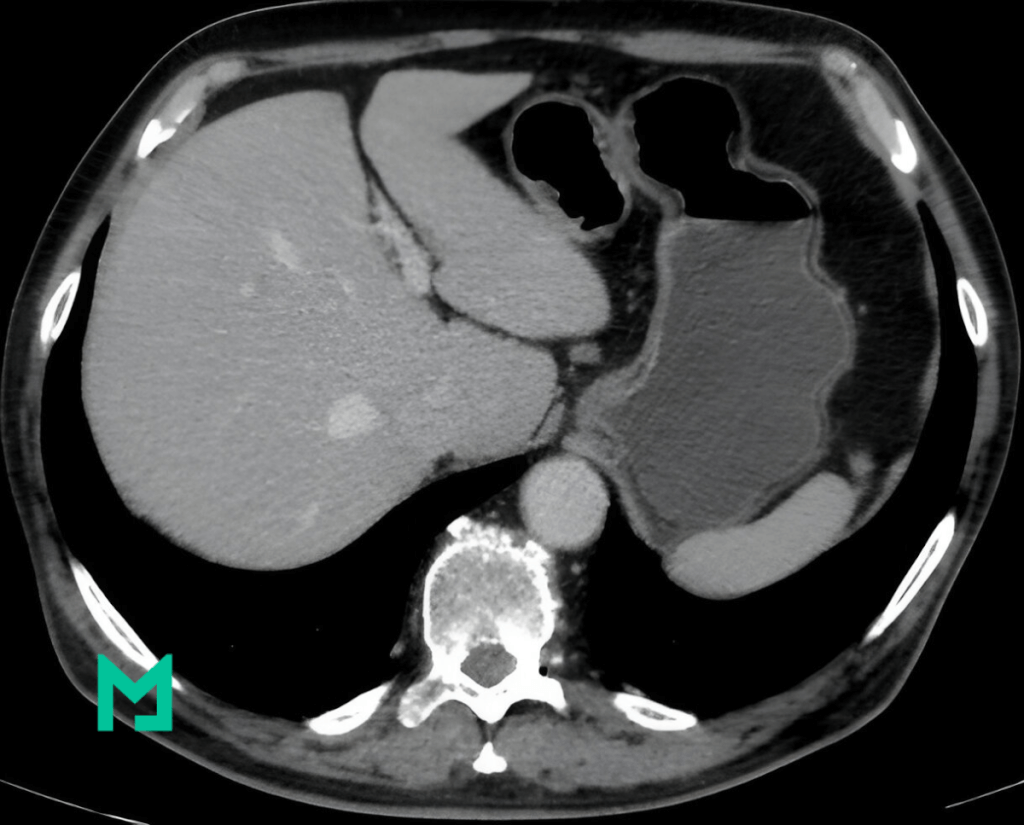

PCCT et Détection des Lésions Hépatiques

Une étude récente publiée dans le Journal of Medical Imaging a exploré les bienfaits du PCCT pour la détection des lésions hépatiques. Les chercheurs ont utilisé des simulations informatiques pour comparer les scans PCCT et EICT de foies présentant diverses lésions. Les résultats étaient impressionnants :

- Détection Supérieure des Lésions : Le PCCT a systématiquement surpassé l’EICT dans la détection des lésions hépatiques, en particulier les lésions petites ou à faible contraste.

- Image Améliorée Qualité : Les images PCCT ont montré un meilleur rapport contraste/bruit et une qualité d’image globale supérieure, facilitant l’identification et la caractérisation des lésions par les radiologues.

- Efficacité du Dosage : Le PCCT a réalisé une meilleure détection des lésions même à des doses de radiation plus faibles, minimisant potentiellement les risques pour les patients.